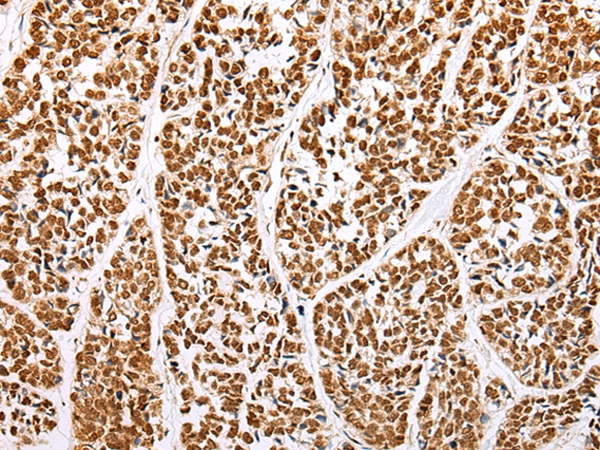

Immunohistochemical analysis of paraffin-embedded Human esophagus cancer tissue using #43463 at dilution 1/35.